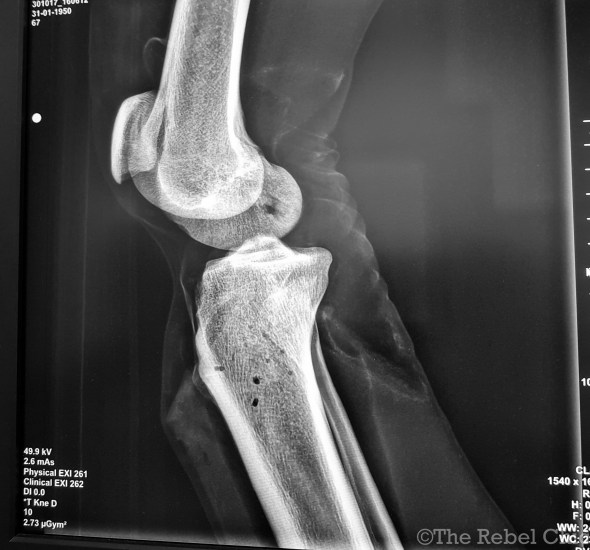

A radiographer is someone who takes X ray images of patients. In addition to that, they also perform CT scan examination and MRI examinations to diagnose for example, an injury. Depending on what country the radiographer is working at, the scope of work task is different. Like for example, here in Norway, the radiographers are very hands on to their patients and they administer medicines and etc. Unlike in the other countries, the radiographer’s only task is to take X rays and report to the radiologist.

A radiologist on the other hand is a medical doctor (a physician) and is a specialist in using medical images to diagnose and treat a disease.